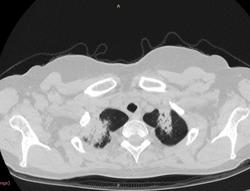

38 лет. 6 лет назад cr носоглотки. Лучевая и химиотерапия. С июля 2012 г. клиника бронхолегочного заболевания.

Флюорография 2010 - норма. В анамнезе хронический гайморит. Бронхоскопия- признаки неспецифического эндобронхита. Исходная флюорография на бумажном носителе с низким качеством изображения. Описаны тени в верхушках легких, воспалительные изменения в средней доле. Лечение макролидами амбулатороно  дало кратковременный эффект.

Срезы по 5 и 7 мм - не лучший вариант для интерпретации интерстициальных диффузных заболеваний. В сканах по 5 мм пропущена центральная часть исследования.